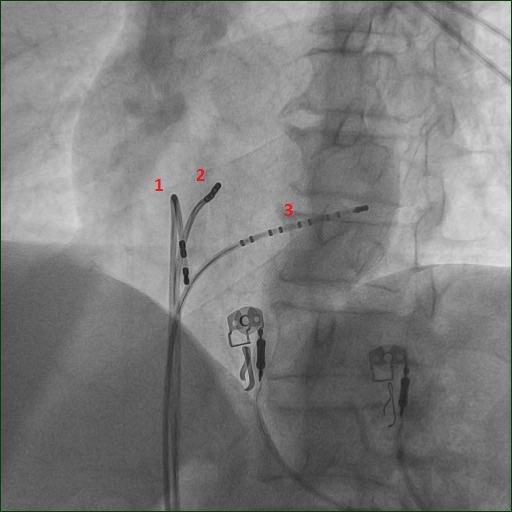

EP catheters placed in the heart

Image: EP catheters placed in the various chambers of the heart. 1. Quadripolar catheter in RV, 2. Quadripolar catheter at His bundle location, 3. Decapolar catheter in coronary sinus